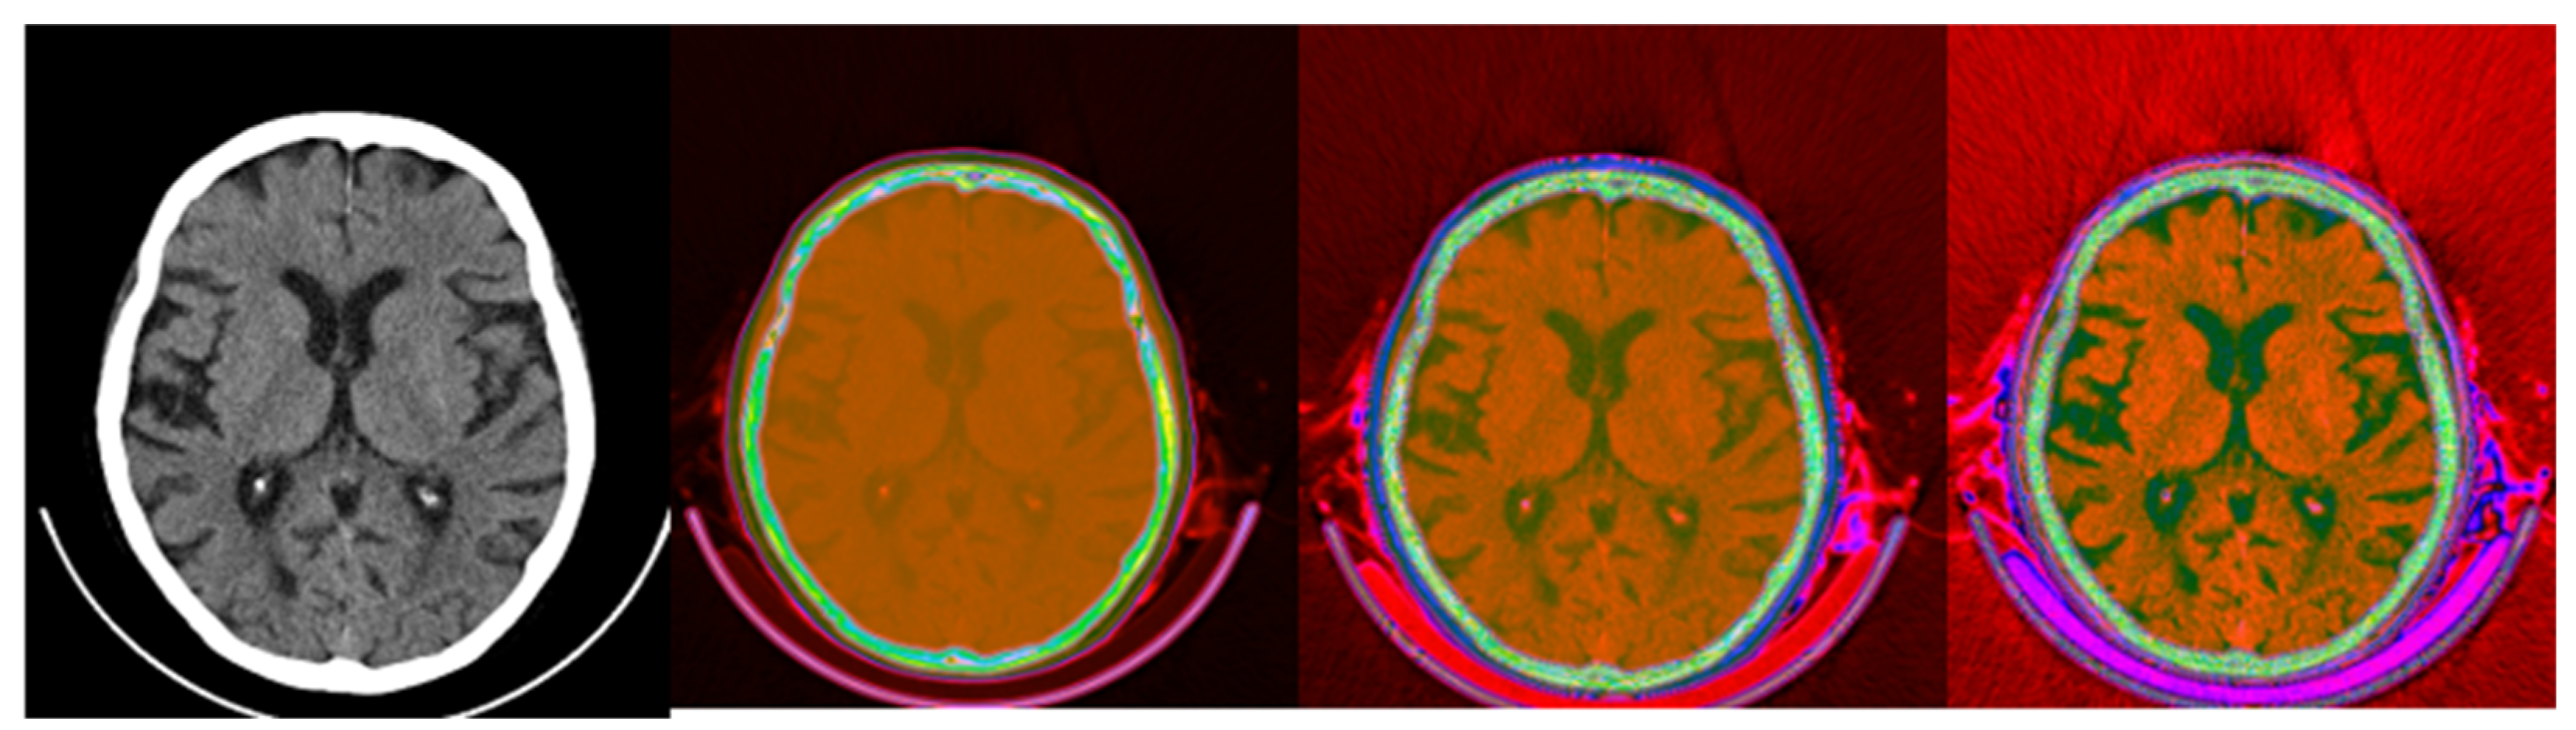

Figure 8.

CIT of brain CT (left block) and corresponding PET (right block). 1. Normalized image of 16-bit integer to 8-bit grayscale 2. Image transformed data by applying window thresholding normalized to grayscale 3. CIT on RGB channels giving priority for the most significant byte to Red Channel, then Green, then Blue using equal distribution of R,G,B levels. 4. Red channel of Image 3. 5. Green channel of Image 3. 6. Blue channel of Image 3.

Figure 8 shows raw, windowed, and CIT-transformed CT and PET slices including their associated color channels. Interestingly, useful information is present in different channels for the two modalities.